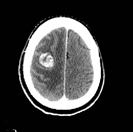

転移性脳腫瘍に対する定位放射線治療例です。

左図:治療前の状態。丸く白く見えるのが腫瘍部分です。